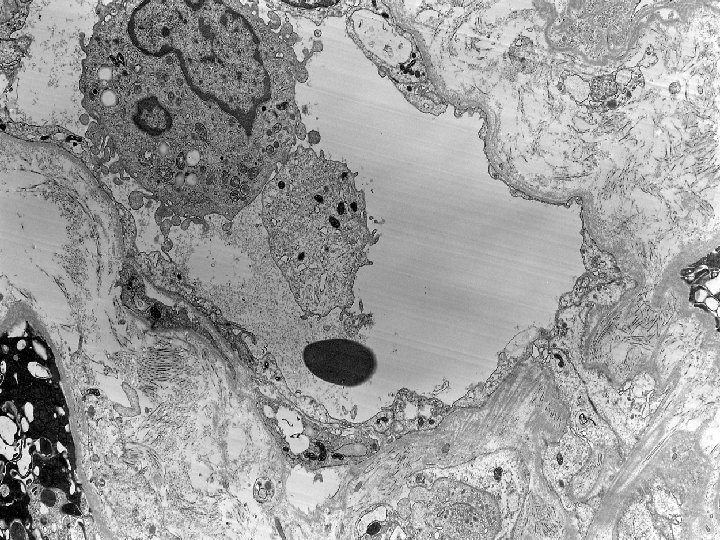

Diagnosis: Renal Biopsy (20 months posttransplantation): Acute tubulointerstitial rejection (Type IB) with signs of

Diagnosis: Renal Biopsy (20 months posttransplantation): Acute tubulointerstitial rejection (Type IB) with signs of acute tubular injury and regeneration. Probable early chronic transplant glomerulopathy, suggested by Electron Microscopy. (G 0 CG 0 I 2 CI 2 T 3 CT 2 V 0 CV 2 AH 0 MM 1)